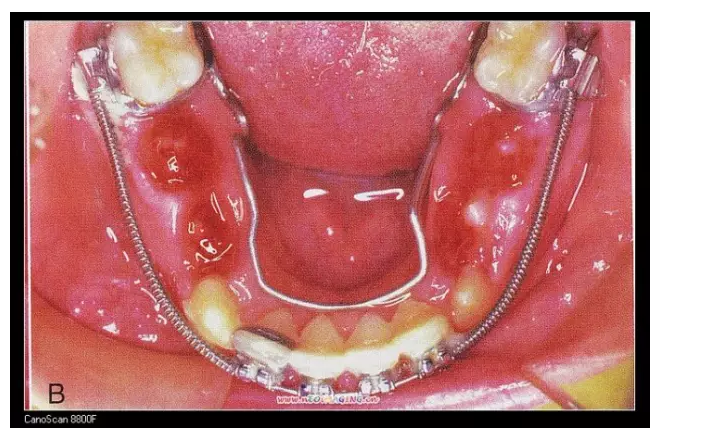

三、擴(kuò)弓器

很多牙列不齊常伴隨牙弓過(guò)窄,所以擴(kuò)弓器是正畸醫(yī)生的好伙伴,它可以以多種形態(tài)和您見面。